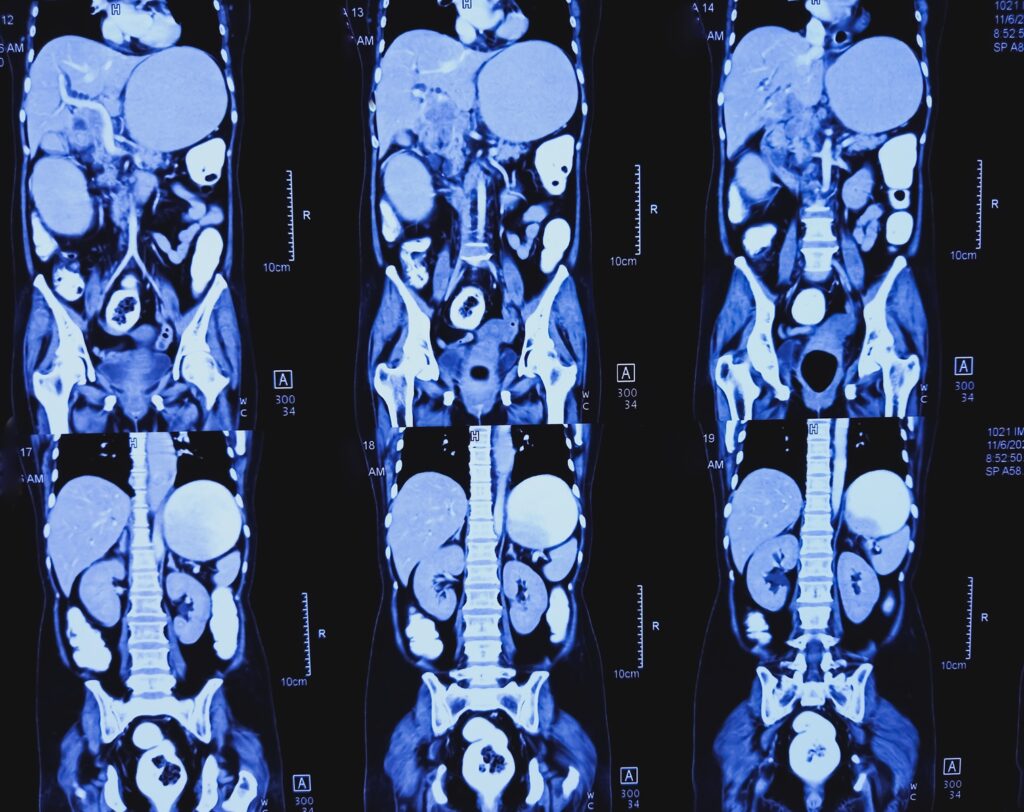

Badania obrazowe: USG, TK i dlaczego czasem potrzebne jest RTG

USG jamy brzusznej i diagnostyka ultrasonograficzna

U wielu pacjentów pierwszym wyborem jest diagnostyka ultrasonograficzna – bezpieczna, szybka, bez promieniowania. Dobrze wykonane usg jamy brzusznej potrafi uwidocznić nieprawidłowy wyrostek, płyn, naciek zapalny czy ropień. W typowym opisie radiologicznym padają sformułowania typu: badanie „pokazuje średnicę wyrostka robaczkowego” powyżej wartości granicznych (często przyjmuje się >6 mm) i cechy zapalenia okołowyrostkowego. Niekiedy w opisie pojawia się też: „w jamie brzusznej stwierdza się niewielką ilość płynu” lub naciek w okolicę wyrostka robaczkowego – co wzmacnia podejrzenie.

Tomografia komputerowa

Tomografia komputerowa ma wysoką czułość, szczególnie gdy USG jest niejednoznaczne (np. u osób otyłych, przy nietypowym położeniu wyrostka lub gdy obraz kliniczny „nie składa się w całość”). Tomografia komputerowa jamy brzusznej pomaga też ocenić powikłania, takie jak ropnia okołowyrostkowego czy cechy rozsiewu zakażenia w obrębie jamy brzusznej.

Jakie badanie jest najlepsze: USG czy tomografia komputerowa?

Często zaczyna się od usg jamy brzusznej. Gdy wynik jest niejasny lub sytuacja kliniczna tego wymaga, lekarz może zlecić tomografię komputerową, która lepiej ocenia trudne przypadki i powikłania.